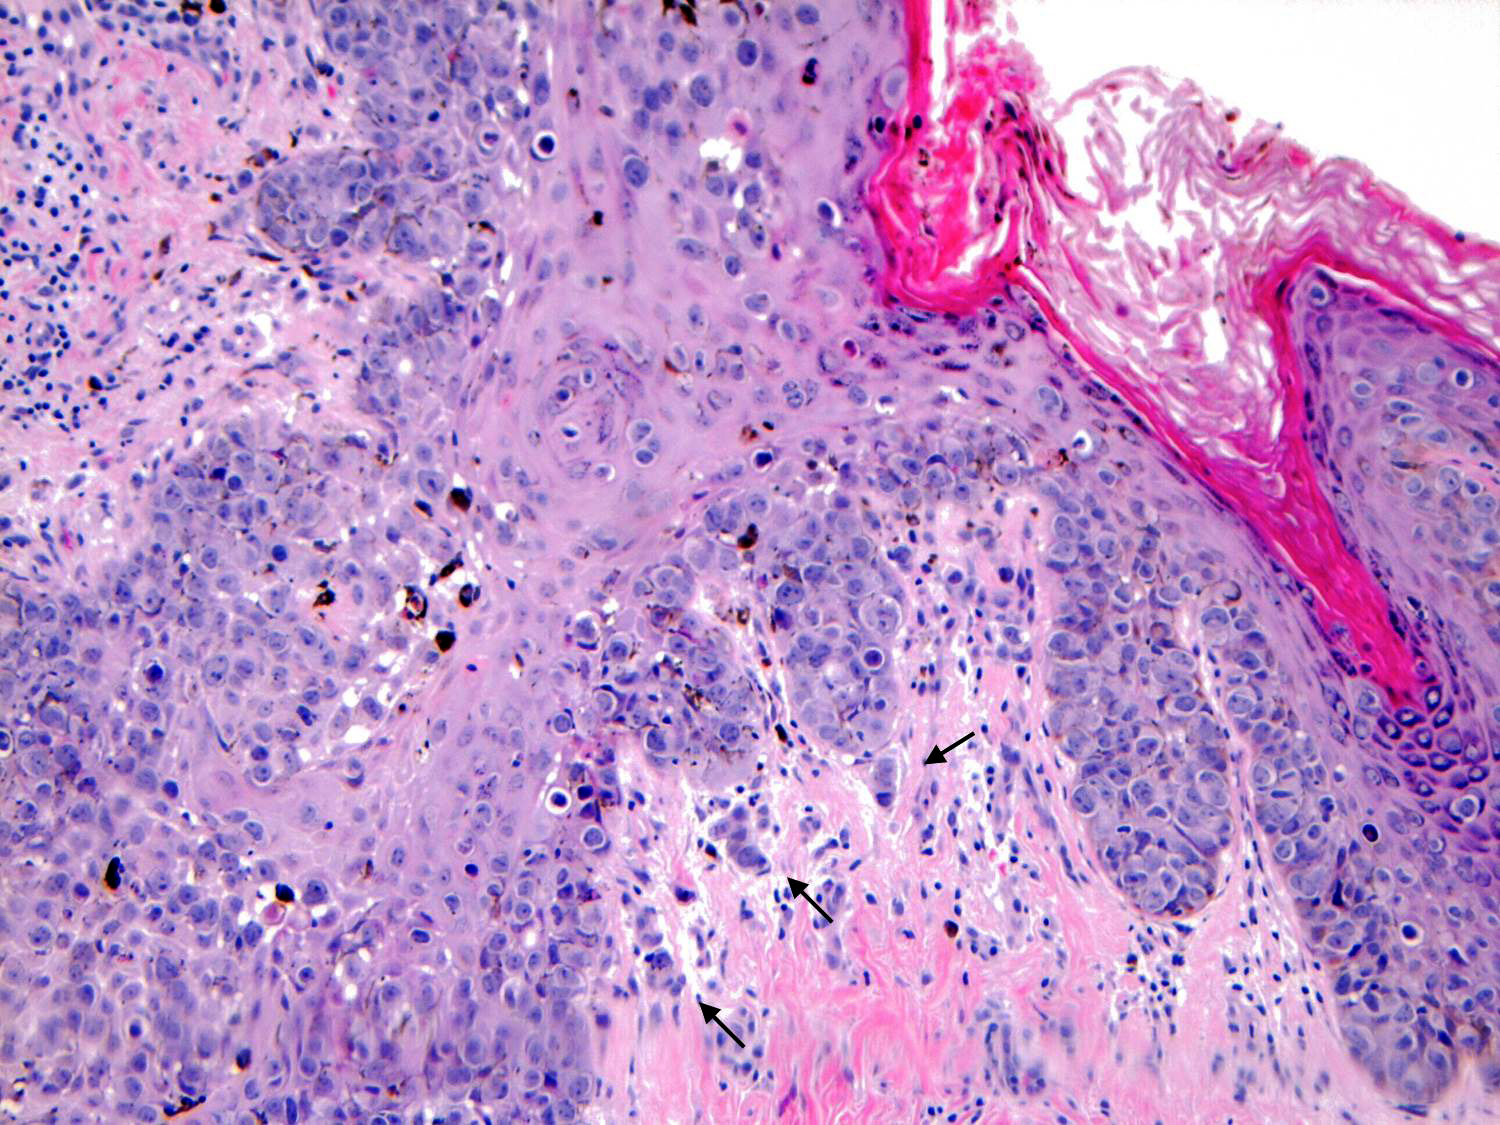

- Paget disease with dermal invasion occurs when Paget cells cross the basement membrane of the epidermis; the invasive component is usually small in size (Arch Pathol Lab Med 2013;137:72)

- Dermal invasion arising directly from MPD in the epidermis and localized to the nipple (invasive Paget disease) is typically detected early and has a favorable outcome (Arch Pathol Lab Med 2013;137:72, Hum Pathol 2014;45:2480)

- Single cells or clusters of cells spread throughout the epidermis

- Cells have abundant pale cytoplasm, large irregular nuclei with prominent nucleoli

- Underlying dermis may have chronic inflammation

Microscopic (histologic) images

Contributed by Anna Biernacka, M.D., Ph.D. and Mary Ann Gimenez Sanders, M.D, Ph.D.